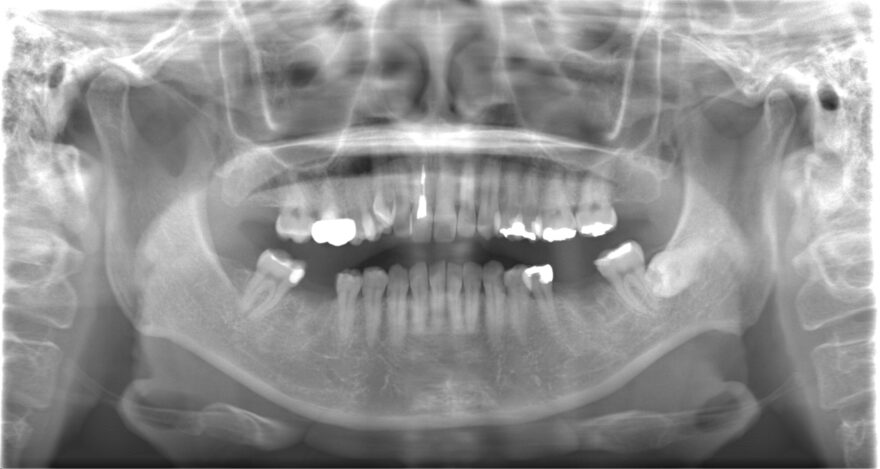

治療後の口腔内写真

左上の八重歯を抜くことで、よりバランスが取れた美しさになりました。